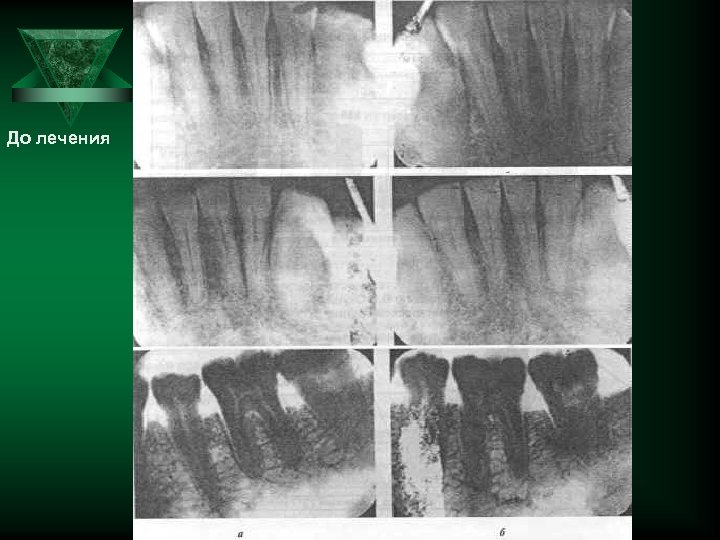

Генерализованный парадонтит Альвеолярная кость Резкая убыль костной ткани Journal of Periodontology Остеотропная терапия при патологии пародонта

Убыль кости при заболеваниях пародонта (по Glickman)

До лечения